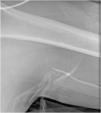

A 64-year-old male patient was admitted to the ICU for vasopressor support and monitoring after undergoing therapeutic lymphangiography due to chylous ascites. On the third day in the ICU, the patient required a peripherally inserted central venous catheter (PICC) for continuous electrolyte infusion, vasopressor support, total parenteral nutrition, and amiodarone. The PICC was successfully advanced 45 cm into the left brachial vein. To confirm the proper placement of the PICC, a bubble test was performed, which was negative. The PICC was partially retired, but the remaining 5 cm were abnormally resistant to extraction. An X-ray was taken, showing the formation of a knot (Fig. 1). Surgical removal was required to extract the PICC (Fig. 2). Catheter knot formation is a rare but a serious cause of catheter occlusion. Rapid identification and prompt surgical management of a knotted PICC can prevent further complications.